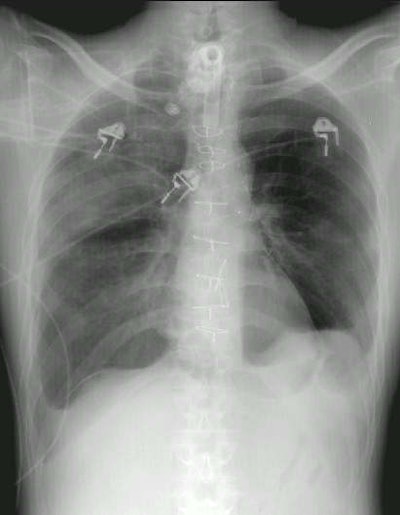

Pneumopericardium:

The patient below demonstrates an example of pneumopericardium. The patient had undergone a prior median sternotomy and coronary artery bypass procedure which resulted in resection of a portion of the pericardium. When the patient developed a right sided pneumothorax (as evidence by the "deep sulcus sign" overlying the right costophrenic angle) the air was able to enter the pericardial sac. Air can be seen surrounding the heart and there is a "continuous diaphragm sign", but the air does not does not extend into the upper mediastinum or neck as would be seen in association with pneumomediastinum.